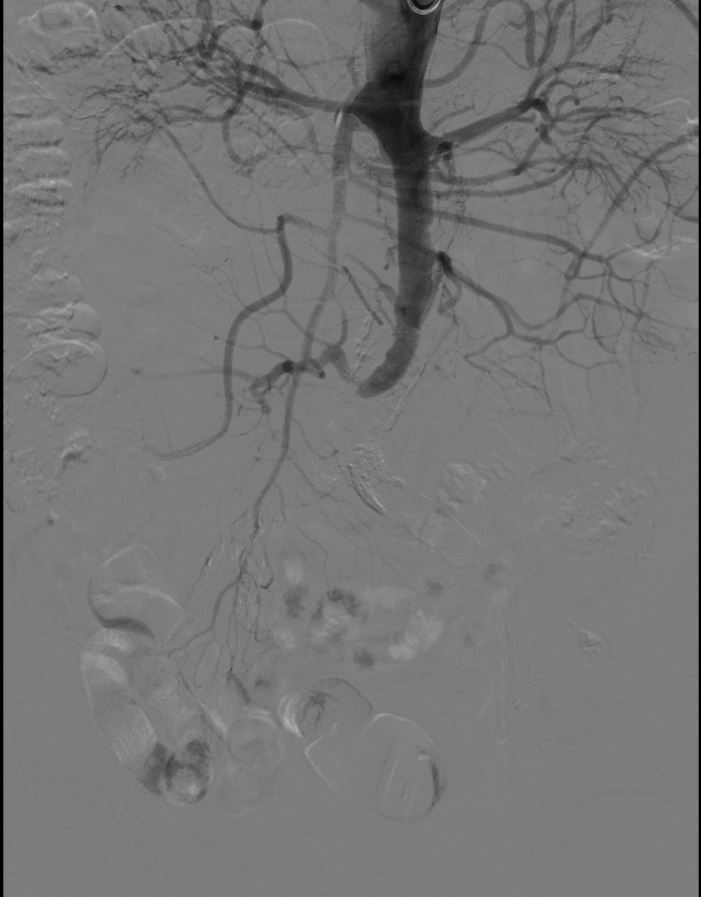

检查结果出来,大家都吓了一跳。从肚子到双腿的大血管,长长一段全堵上了!诊断很清楚:勒里施综合征。 「截肢?」 张爹一听,脑子「嗡」的一声,似乎看见自己坐着轮椅的样子,心凉了半截。

几个科的专家一起商量。经过反复评估和推演,定了方案:上,用创伤小、恢复快的微创手术-腹主动脉-双髂动脉分叉血管腔内覆膜支架重建术(CERAB 技术)!

手术当天,介入手术室里气氛紧张。麻醉由于大朋主任坐镇,车星主任操控着导丝导管,细心打通堵塞的血管。最终,凭借娴熟的技术,把支架精稳稳放进去,血流「哗」的一下通了!